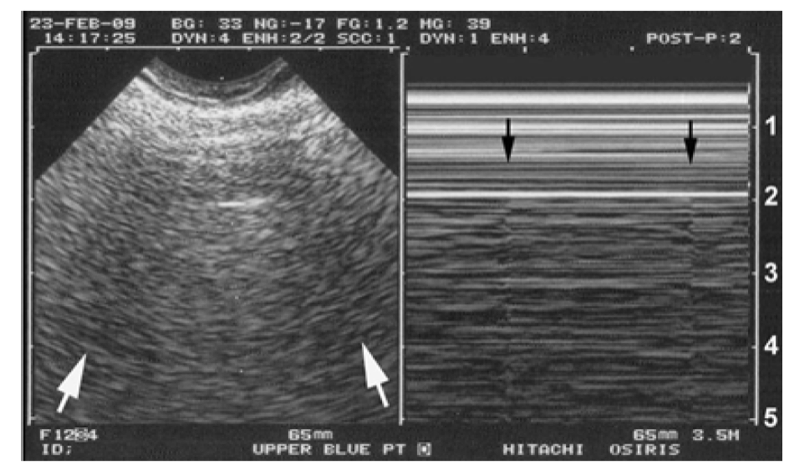

4. उपचर्म वातस्फीति: मोसेलिन प्रकार

इस मामले में गैस की मात्रा कोमल ऊतकों पर आक्रमण करती है, और यह प्ल्यूरल लाइन का पता लगाने में बाधा डालती है: उपचर्म वातस्फीति LUCI में एक मुख्य बाधा है। इसका एक संभावित उत्तर है। हड्डियाँ मौजूद हैं, जो एक कठोर और गहरी योजना बनाती हैं। बशर्ते कि यह रोगी को नुकसान न पहुँचाए, हम गैस को छिपाने के लिए पसलियों की ओर दबाव के साथ जांच करते हैं। इससे अचानक एक अस्पष्ट चमगादड़ चिह्न का पता चल सकता है। यह चिह्न, जिसे "कोहरे में चमगादड़" कहा जाता है, उतना ही मूल्यवान हो सकता है जितना कि कोहरे में खोए हुए तनावग्रस्त पायलट के लिए कोहरे के बीच रनवे का अचानक पता लगना (अंजीर 2).

चित्र 2 कोहरे में चमगादड़ और टी-लाइनें। इस स्पष्ट रूप से चुनौतीपूर्ण आकृति में कई चीजें दिखाई देती हैं। इस मरीज को एक आघात के बाद - काफी गंभीर उपचर्म वातस्फीति थी। बाईं छवि (वास्तविक समय) की व्याख्या करना काफी असंभव था। पसलियों के पिंजरे की ओर जांच को दबाने पर, अस्पष्ट छवियों का पता लगाने का एहसास होता है जो पसलियों की ध्वनिक छाया (उठते सफेद तीर) के अनुरूप हो सकती हैं। संभवतः पसलियों की रेखा के नीचे, एक हाइपरइकोइक, क्षैतिज रेखा, अस्पष्ट रूप से, दिखाई दे रही है, संभवतः फुफ्फुस रेखा (दाएं ऊर्ध्वाधर पैमाने के 2.0 सेमी)। दाईं ओर, एम-मोड छवि में, बहुत हल्की दुर्घटनाएं दिखाई देती हैं, जो ठीक इसी रेखा (काले तीर) से आती हैं या नीचे से ऊपर तक देखने पर, ठीक इसी रेखा (दाएं पैमाने के 2.0 सेमी) पर रुक जाती इस बेहद चुनौतीपूर्ण फ़ाइल में, चमड़े के नीचे की वातस्फीति से पीड़ित एक आघातग्रस्त मरीज़ से, और इस अत्यधिक बाधा के बावजूद, पसलियों की परछाई और फुफ्फुस रेखा ("कोहरे में चमगादड़") और फेफड़ों की नाड़ी को परिभाषित किया जा सकता है। महत्वपूर्ण अल्ट्रासाउंड के नियम भ्रम की कोई गुंजाइश नहीं छोड़ते: कोई न्यूमोथोरैक्स नहीं होता।